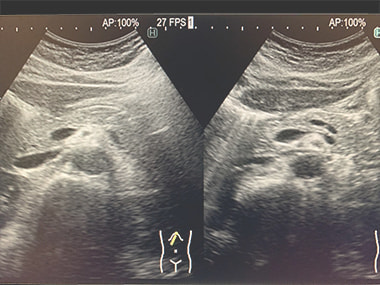

腹部エコー検査:

腹部臓器(肝臓・胆のう・膵臓・腎臓・脾臓)、腹部大血管、骨盤病変(膀胱・前立腺・子宮・卵巣)、リンパ節などに異常病変がないかを検査します。